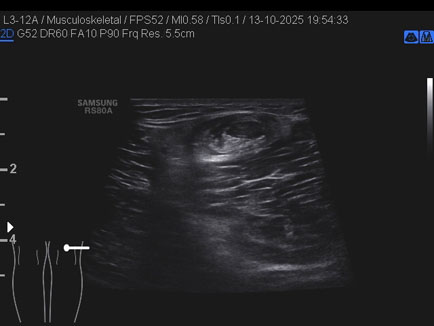

Data inserimento: 16/10/2025

Ecografia del: 13/10/2025

Strumento: Samsung

Sonda: Lineare

Commento all'esame: giovane atleta con referto di RMN che riporta cisti del semimembranoso/gemello e falda fluida lungo il gemello mediale medesimo.

Alla ETG:

A. formazione cistica di circa 22 x 17 x 23 mm (DAP x DT x DL = 4.5 ml) indovata tra il semimembranoso ed il gemello mediale: borsite dei tendini suindicati; assenza di falde fluide a carico dello sfondato sottoquadricipitale!

B. rottura completa del semitendinoso in sede distale con diastasi dei monconi di circa 25 mm.

Conclusioni: lesione e cisti del muscolo semitendinoso destro (right semitendinosus muscle injury and cyst).